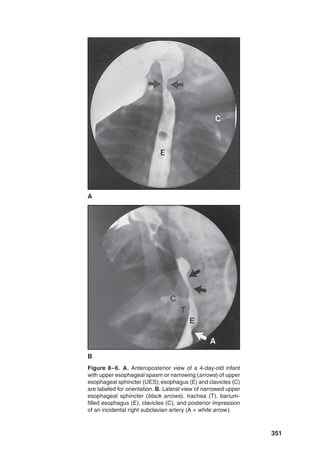

Figure 2–3. Posterior sketch of the upper aerodigestive tract

(larynx and pharynx). Pathway for food bolus is around the

larynx and down the channels made by the pyriform sinuses,

which elongate during the act of swallowing. The bolus is

moved through the upper esophageal sphincter (UES) par-

tially via action of the hyolaryngeal complex decreasing ten-

sion on the open UES while the larynx is closed and protected

high in the neck under the tongue base.